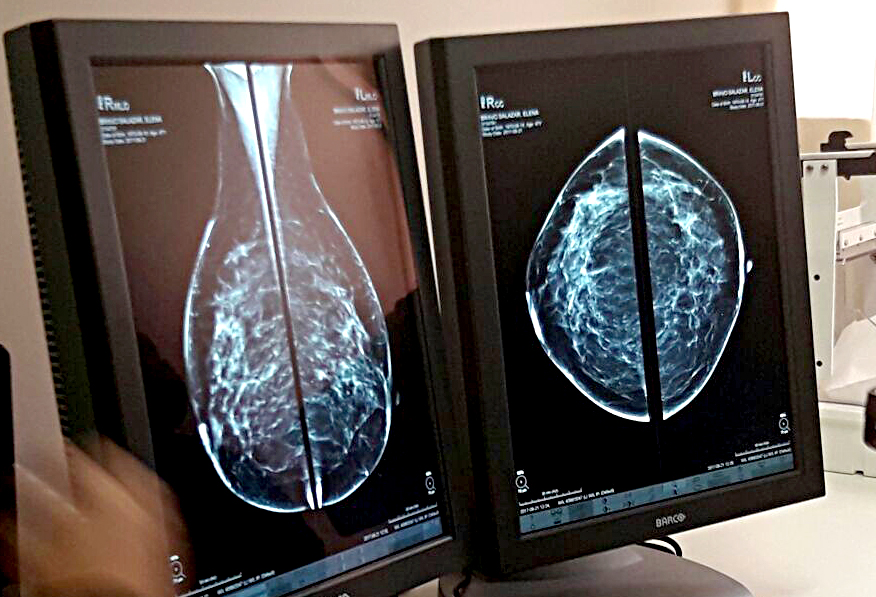

Lima, Perú.- El Ministerio de Salud (Minsa) informó que a la fecha se han realizado 1056 telemamografías, a igual número de pacientes mujeres, para el diagnóstico oportuno del cáncer de mama. Estos exámenes se realizan en diez hospitales del interior del país y las imágenes son evaluadas por especialistas en el Hospital de Emergencias Villa El Salvador (HEVES), en Lima.

A través del uso de las tecnologías de la información y comunicación (TICs), las imágenes de las mamografías, se envían electrónicamente al centro de lectura e interpretación del HEVES, en donde un equipo de radiólogos realizan el diagnóstico oportuno y recomiendan el tratamiento que deben seguir las pacientes con resultado positivo para el cáncer de mama.